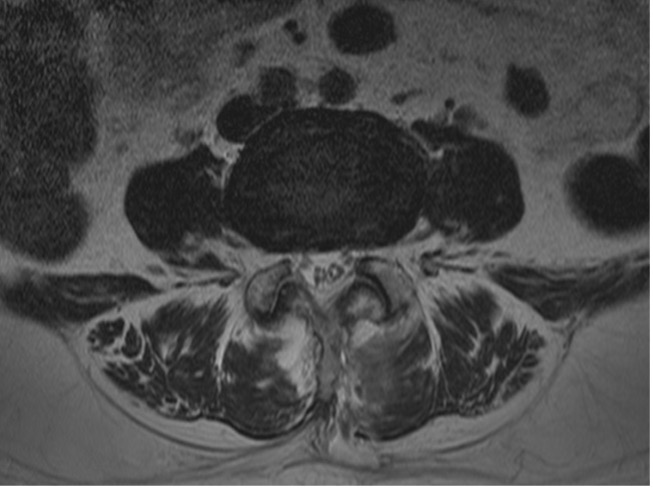

수술 전

수술 후